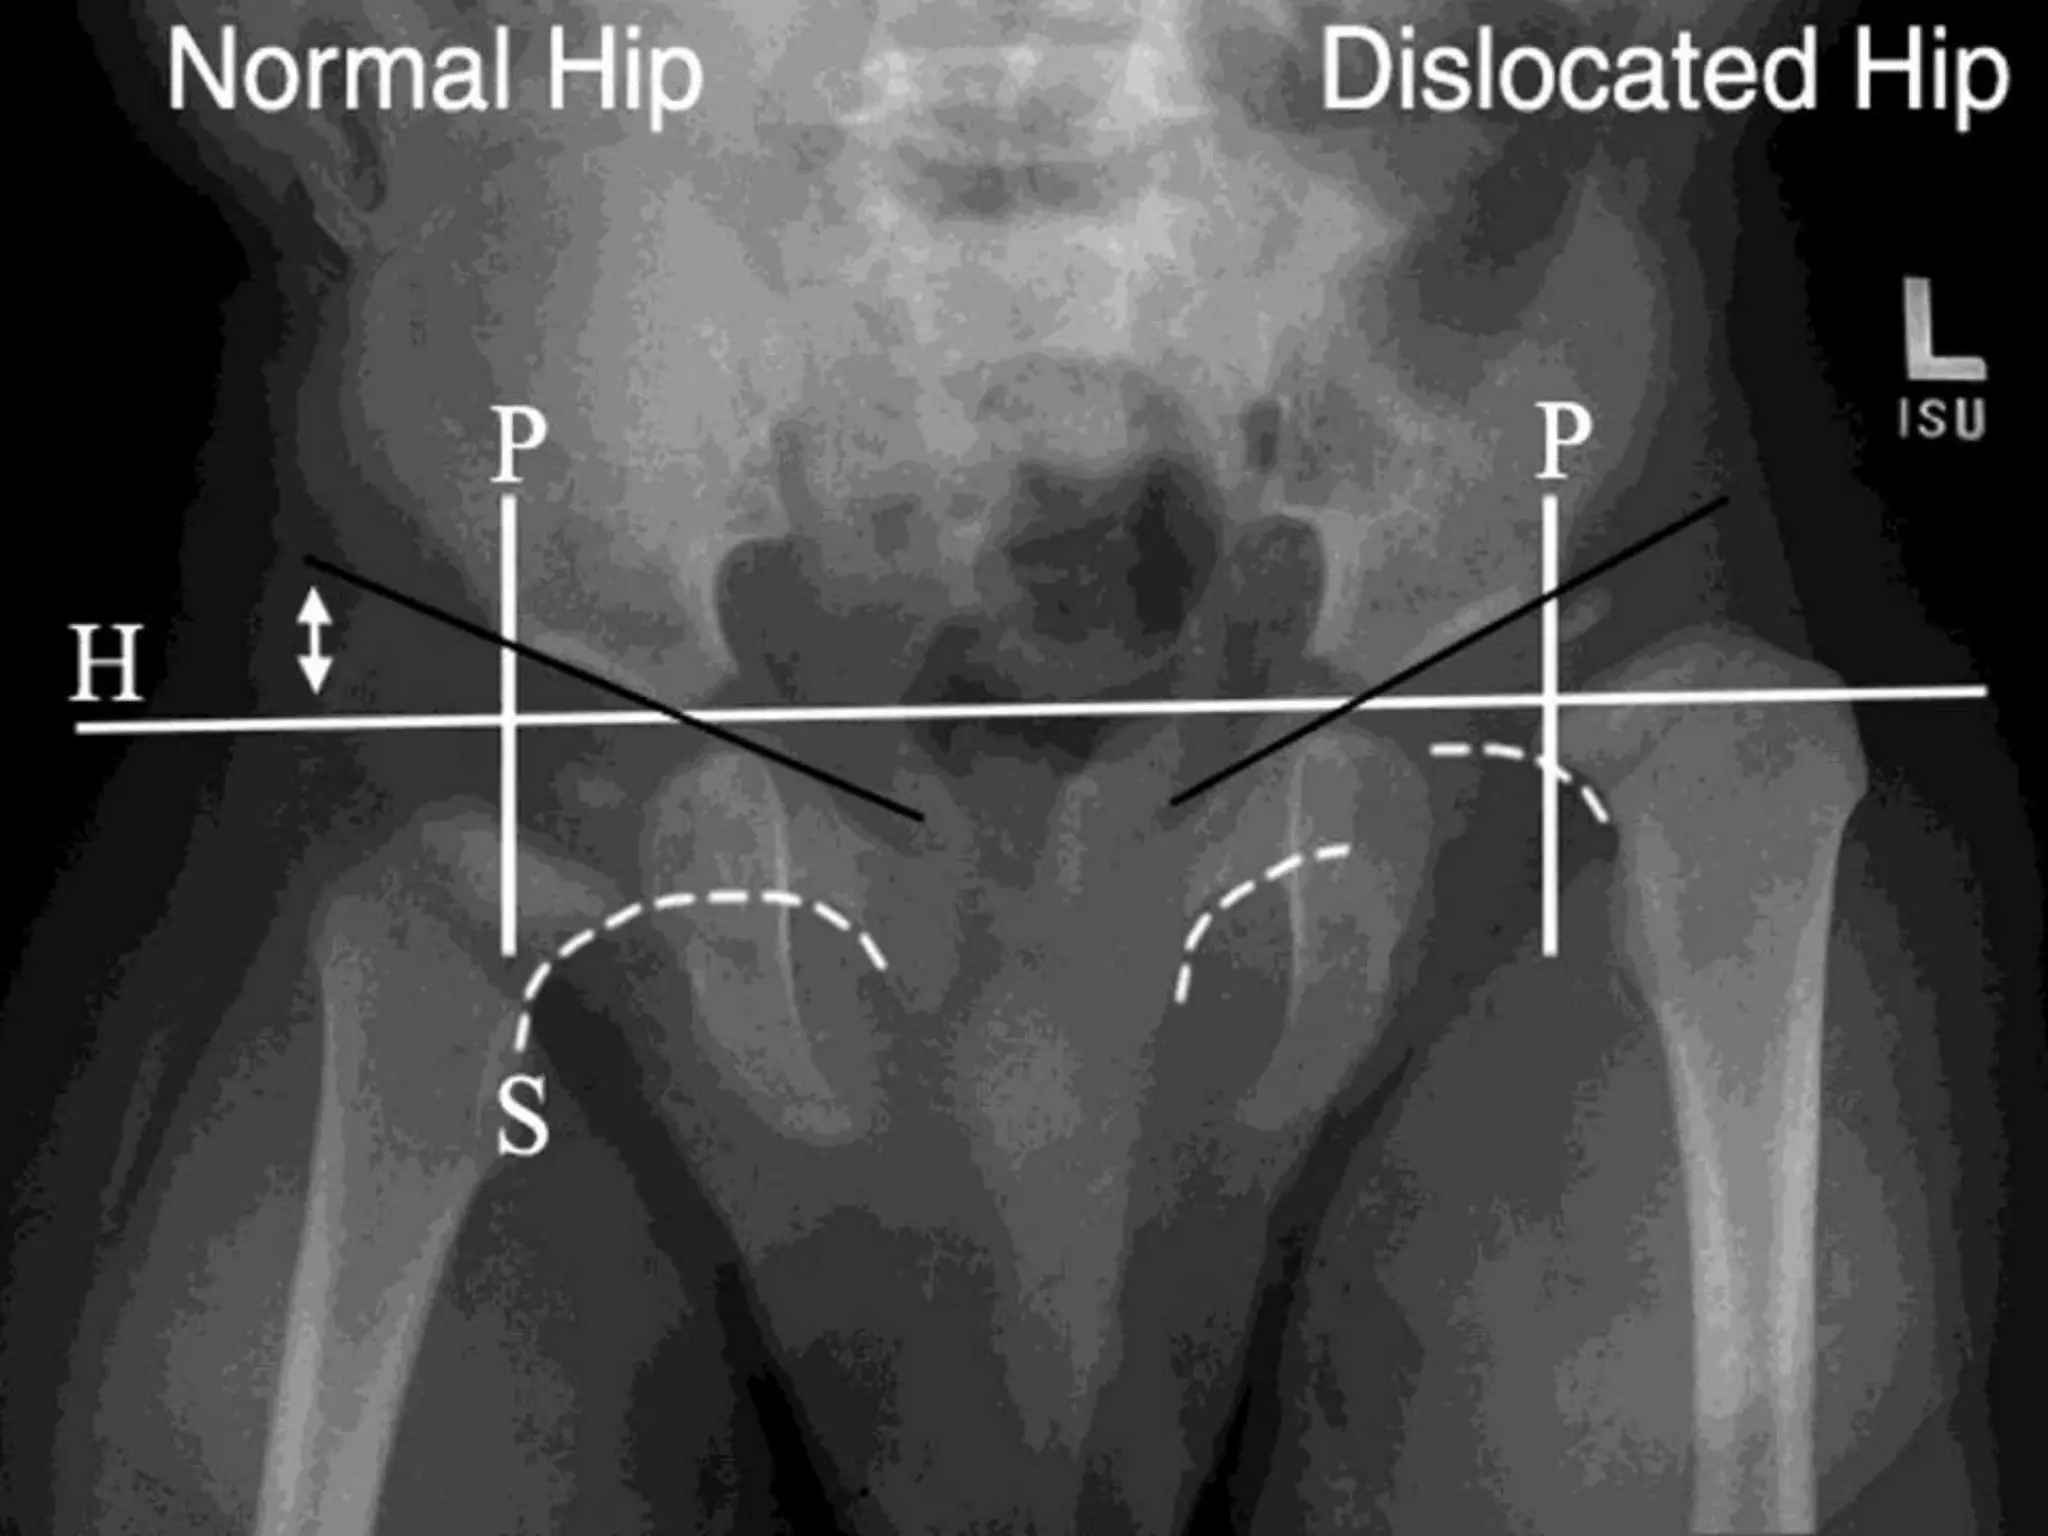

X-RAY- IN CDH/DDH

High resolution Ultrasound

(HRUS):

- Preferred modality in newborn:

- Help to identify mild subluxation

and acetabular dysplasia.

- Progression of treatment